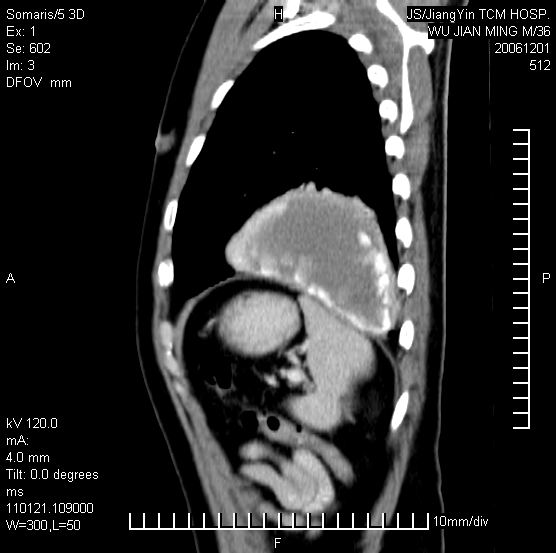

以下是引用dyqct在2006-12-1 21:17:00的发言:[br]左心缘旁及后肋膈窦区见巨大椭圆形混杂密度肿块,周围见大小不等斑片状钙化,内部无强化,周围包膜轻度强化,心脏明显受压变形,即明显占位效应,肿块广基与心包、膈相连。肝、脾内、肝门见多数小结节状钙化影。[br]考虑:1、左心缘旁及后肋膈窦区慢性包裹性胸膜炎(结核性);[br] 2、肝、脾及肝门淋巴结核已钙化。[br]

以下是引用zrs在2006-12-2 17:28:00的发言:[br]肺内、肝脾内虽有钙化,但不支持结核性胸胸膜炎包裹,而支持寄生虫感染![br][br]

以下是引用zyx168在2006-12-2 10:10:00的发言:[br][br]肝脾肺内多发钙化灶